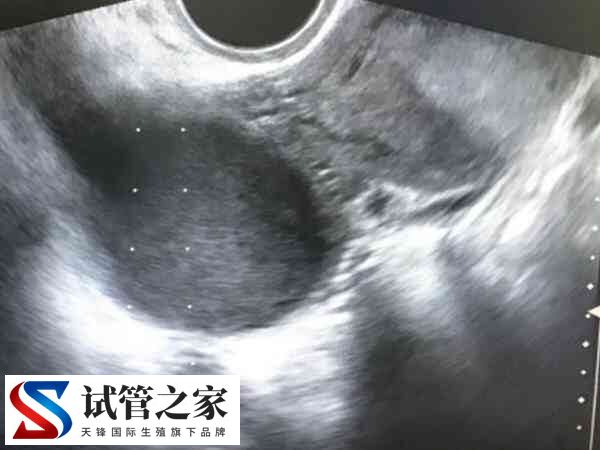

子宫内膜异位症指有活性的内膜细胞种植在子宫内膜以外的位置,而形成的一种女性常见妇科疾病,一般来说,该疾病表现的症状为痛经、月经异常、不孕和性交疼痛等。虽然会影响生育能力,但是可以通过试管婴儿实现生育。